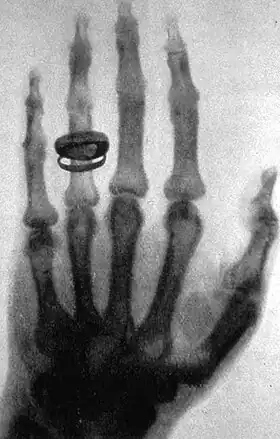

1896: The first radiograph used to assist in surgery is taken in Birmingham by the British pioneer of medical X-rays, Major John Hall-Edwards thus kick-starting a whole new field of medical science.